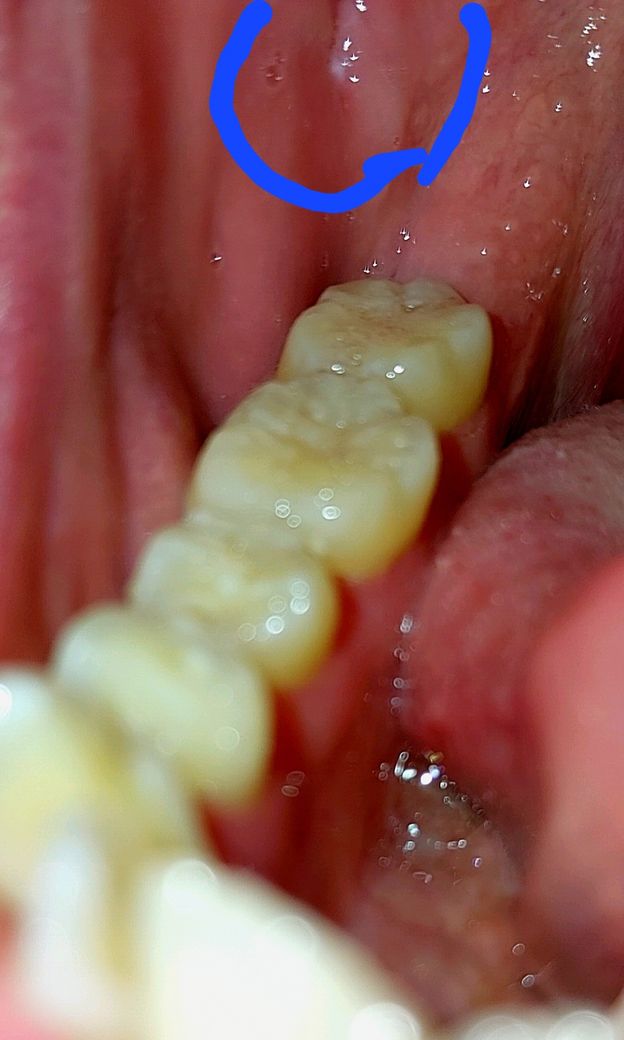

첫번째사진은 편도쪽사진이고, 두번째 사진이 입안흰점 발견초반모습이고 , 세번째가 요즘입니다.

• 3번 째 사진

편도결석의 가능성이 있습니다.

편도결석은 편도 내부에서 상피 조직 파편이 모여 노란 알갱이를 형성하는 상태를 나타냅니다. 주로 만성 편도염으로 인해 발생하며, 편도에 있는 작은 구멍인 '편도와'가 커지면 음식물 찌꺼기가 끼여 세균 번식에 적합한 환경이 형성됩니다. 이러한 세균의 모임이 노란 알갱이를 형성하게 됩니다. 편도결석은 구강 위생이 미흡한 사람, 비염 또는 부비동염으로 인한 후두 분비물이 있는 사람에게서 주로 나타납니다.

편도결석은 입안에서 노란 알갱이 형태로 나타나며, 구역질이나 기침 시 노란 알갱이가 나올 수 있습니다. 다른 증상으로는 입냄새, 인후통, 귀 통증 등이 있을 수 있습니다. 또한, 침을 삼킬 때 목에 이물질이 걸린 느낌이나 목의 간질거림이 발생할 수 있습니다.

편도결석은 구강 검진 시 목젖 양 옆의 편도에서 노란 알갱이로 확인됩니다. 이를 통해 진단이 가능하며, 때로는 편도염도 동반될 수 있습니다. 구강 및 인두 진찰 및 내시경 검사를 통해 진단할 수 있습니다.